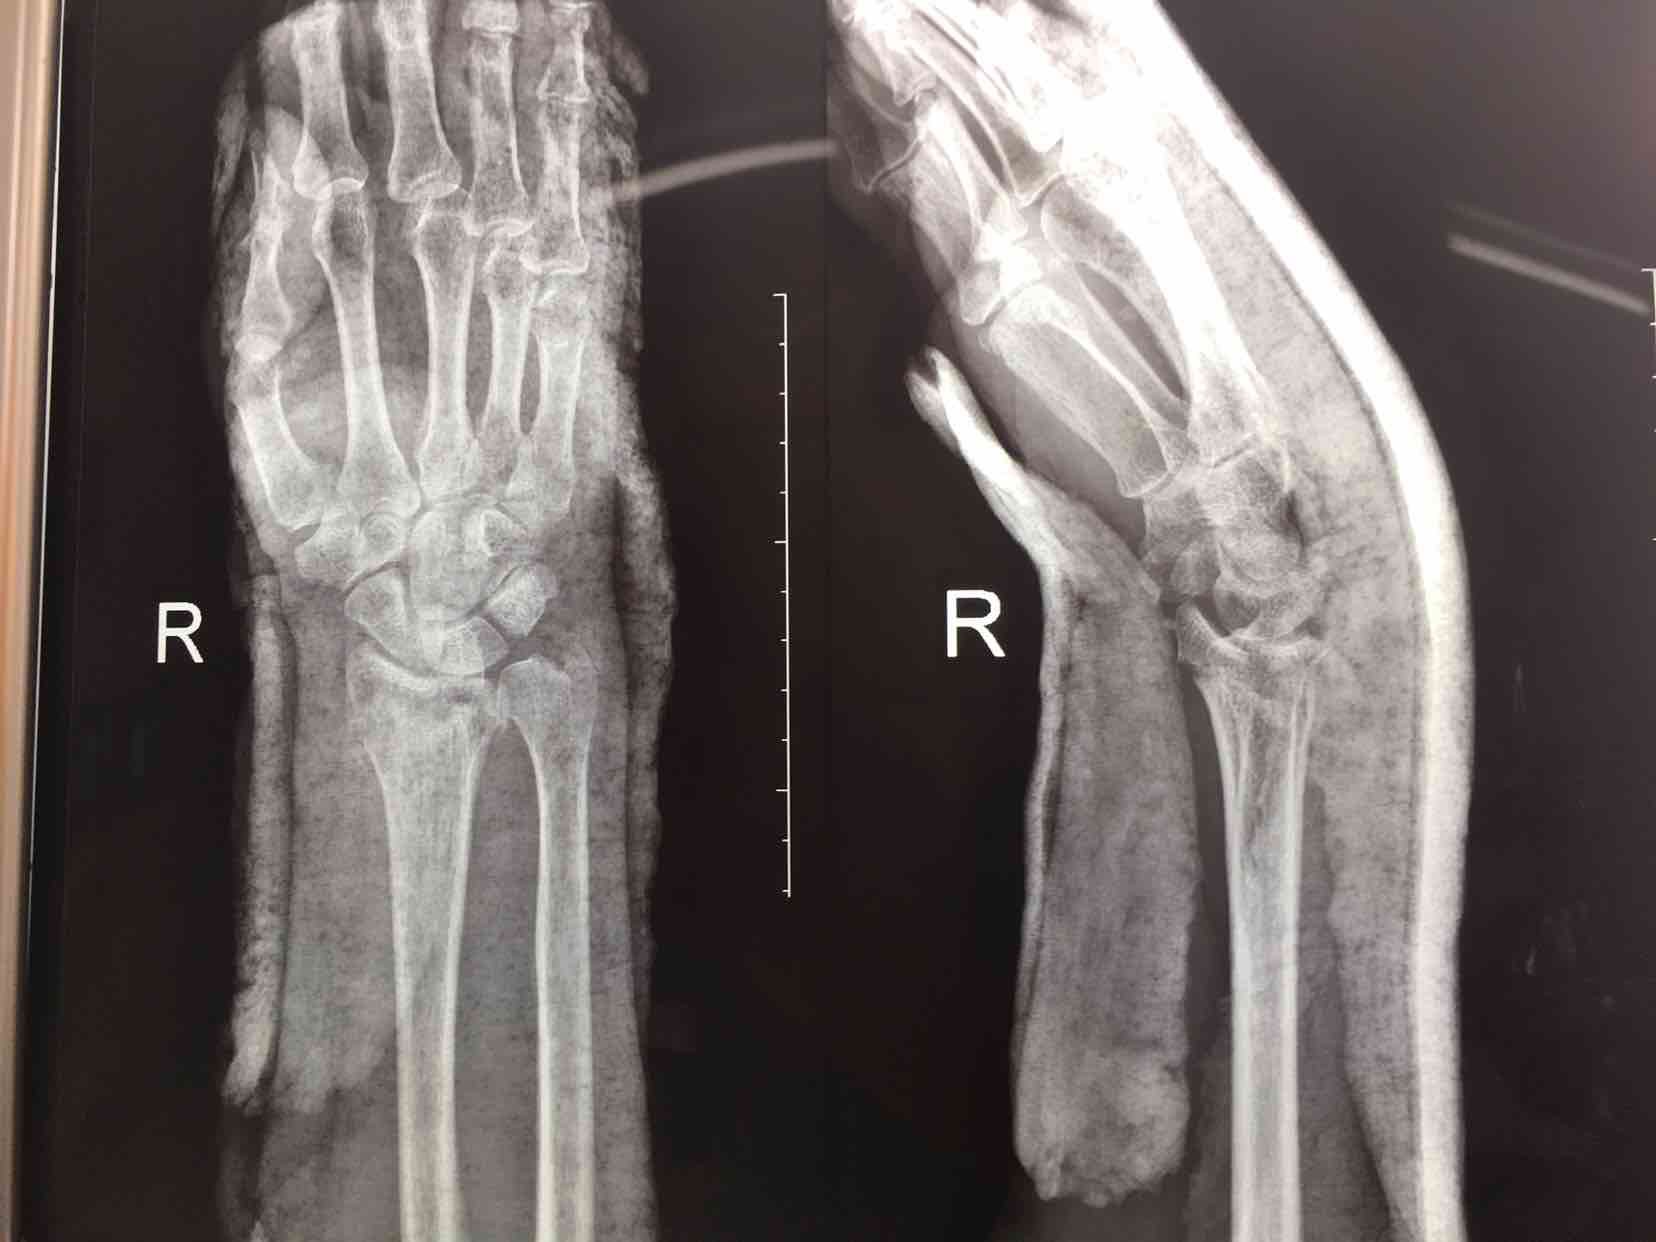

摔伤后腕部肿痛,活动受限4天入院。4天前在外院行手法整复,复查关节面塌陷,尺偏角掌倾角变小,后来我院就诊。

诊断:右侧克雷氏粉碎性骨折完善术前准备,在臂丛麻醉下行切复内固定术,术后抗炎,消肿等对症处理。